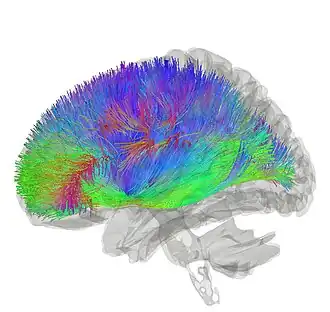

Tractography showing corticostriatal connections